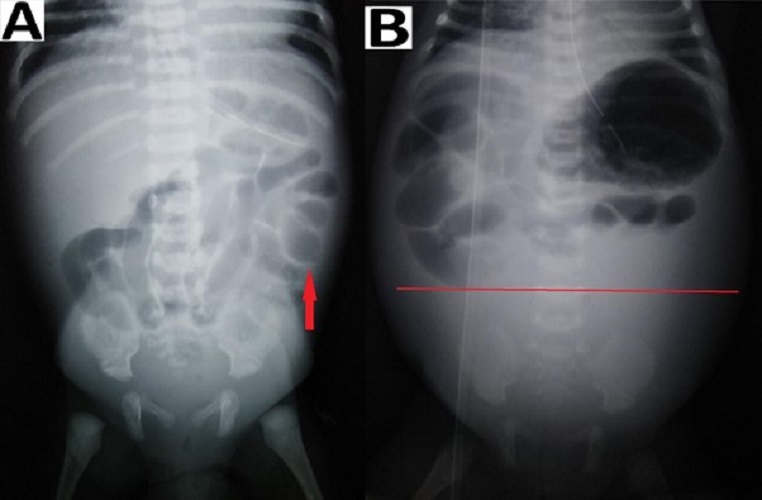

Intestinal distension, often secondary to obstruction, is the most common sign visible in 90% of radiograms in neonates with NEC.[2] Although no evidence-based guidelines are available regarding the duration and frequency of radiographic examination, an attempt was made by Coursey et al. in 2009 using a ten-point scale for abnormal radiographic findings in infants with clinically suspected NEC.[24] They called it Duke’s Abdominal Assessment Scale (DAAS score). Findings of fixed (unchanging) bowel loops, definite pneumatosis, or portal venous gas as revealed by DAAS scores of 7, 8, or 9 were highly associated with eventual surgical intervention for suspected NEC.[25] Bowel wall thickening from oedema and haemorrhage is seen as separated bowel loops on radiographs. [15] Increased bowel wall thickening on radiographs in presence of clinical features is an early sign of NEC (Fig. 4). A wall thickness greater than 2.6 mm is a pathological finding on ultrasound. [21]

Intestinal pneumatosis is a pathognomonic sign for NEC. According to different sources, detecting this sign in ultrasound varies between 13% and 100%, while in radiograms, it ranges from 20 to 95%.[21] A linear (crescent) gas pattern (Fig. 5) is a more specific sign than the bubbly (foamy) gas pattern.[15]

We detected fixed bowel loops in 3 patients (18%) pneumatosis intestinalis (Fig. 5) in 1 (6%), portal venous gas in 1 (6%), and massive ascites (Fig. 4) in 2 patients (12%) among the group B (with the absence of pneumoperitoneum). These percentages (findings) were relatively small in our study, but in presence of clinical signs, they contributed towards deciding to operate in our study. Thus collectively (clinico-radiologically), more than one sign according to Modified Bell’s staging was present in group B patients, i.e. 8 (50%) stage IIIA, 12 (75%) stage IIB, 1 (6%) stage IIA and 3 (18%) stage IA/IB.

Figure 4

Preoperative radiographs showing: (A) increased bowel wall thickening (red arrow) and (B) dilated small bowel loops in the upper abdomen with ground glass appearance in the lower abdomen (below the red line).

Figure 5

Radiographs showing (A) pneumatosis intestinalis with linear gas pattern (black arrow) and (B) bubbly gas pattern (black arrow).